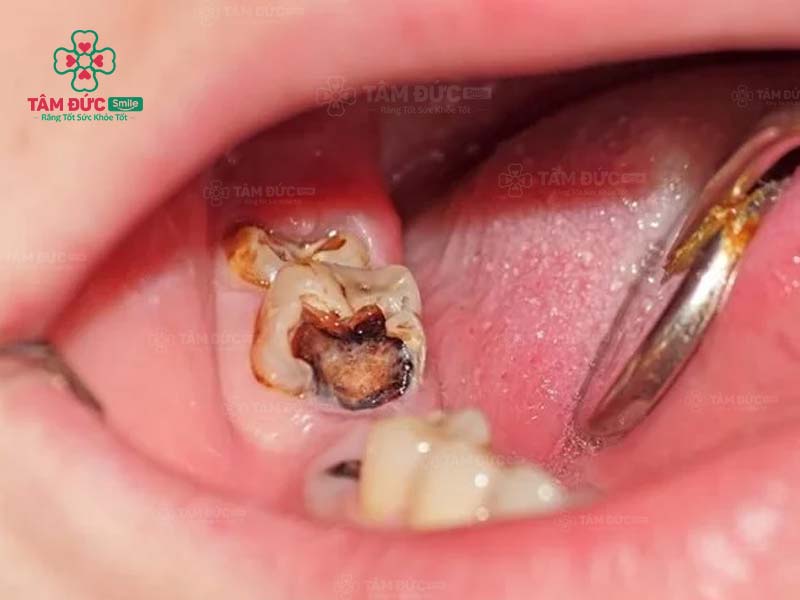

15. Trám răng có cần phải diệt tủy răng hay không?

Trám răng cần diệt tủy răng chỉ áp dụng đối với các trường hợp phải điều trị tủy. Nếu tủy của Quý khách bị viêm nhiễm, thì việc diệt tủy trước khi trám răng là rất cần thiết. Bác sĩ sẽ loại bỏ toàn bộ mô tủy đã chết để giúp Quý khách đảm bảo sức khỏe răng miệng.

Nếu Quý khách chỉ trám răng trong trường hợp răng bị sứt mẻ nhẹ hoặc răng thưa thì không cần diệt tủy răng. Vì quy trình trám răng chỉ tác động đến bề mặt răng, ngoài ra tủy răng của Quý khách cũng đang rất khỏe mạnh.

Nếu sâu răng đến tuỷ, bác sĩ buộc phải lấy tuỷ răng trước khi trám